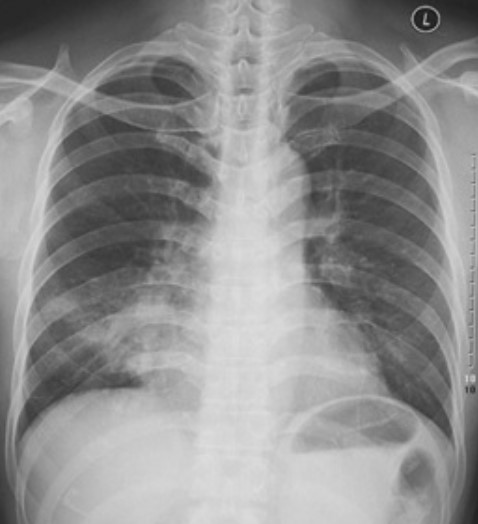

4.根据下图请做出正确诊断

A.右侧肺炎

B.两下肺炎

C.右下肺肺癌

D.正常胸片

答案提示:【该题针对“ X线-肺炎 ”知识点进行考核】